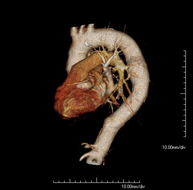

Prueba diagnóstica no invasiva que consiste en el estudio de la arteria aorta abdominal obteniendo imágenes de alta definición anatómica mediante el empleo de un equipo de TC (Tomografía Computarizada) y de contraste yodado. La calidad de las imágenes permite realizar reconstrucciones en 2D y 3D gracias a estaciones de trabajo especializadas en el estudio arterial. Está indicado en aquellos pacientes con enfermedad vascular (aterosclerosis), en aneurismas de aorta, en pacientes con dolor abdominal de posible origen vascular, en estudios pre-quirúrgicos de lesiones adyacentes a la aorta abdominal como "mapa" vascular, etc. La información obtenida de forma no invasiva es indispensable para los pacientes que requieren tratamiento percutáneo o quirúrgico. En aquellos pacientes que solo requieren un seguimiento de las lesiones vasculares, esta técnica es la técnica no invasiva de elección junto con la angio-RM. - Angio-TC arterias renales

Prova diagnòstica no invasiva que consisteix en l'estudi de l'artèria aorta abdominal amb l'obtenció d'imatges d'alta definició anatòmica mitjançant l'ús d'un equip de TC (Tomografia Computaritzada) i contrast iodat. La qualitat de les imatges permet realitzar reconstruccions en 2D i 3D gràcies a estacions de treball especialitzades en l'estudi arterial. Està indicat en aquells pacients que pateixen malaltia vascular (arteriosclerosi), aneurismes d'aorta, en pacient amb dolor abdominal d'un possible origen vascular, en estudis prequirúrgics de lesions adjacents a l'aorta abdominal com el "mapa" vascular, etc. La informació obtinguda de forma no invasiva és indispensable per als pacients que requereixen tractament percutani o quirúrgic. En aquells pacients que només requereixen un seguiment de les lesions vasculars, aquesta tècnica és la tècnica no invasiva d'elecció juntament amb l'angio RM. - Angio TC d'artèries renals